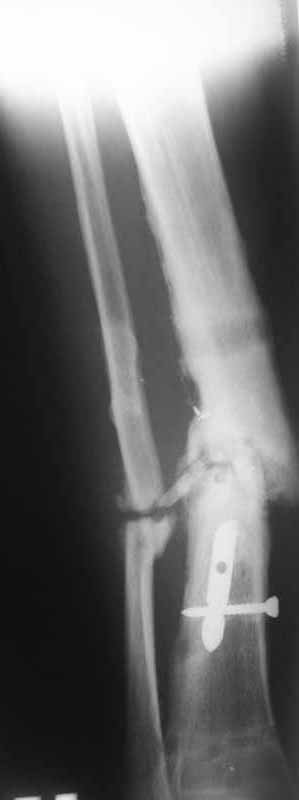

Уважаемые коллеги благодарю Вас за проявленный интерес к данной проблеме! Пересылаю Вам внешний вид правой голени.

Как-то вот нет уже желания открываться в зоне ложного сустава. Мы бы

попытались сделать закрыто. Винт в дистальном отломке удалить через прокол.

Кусок гвоздя оставить. Новый гвоздь (солидный), возможно с покрытием.

Примерная ситуация. Пациент 37 лет. Синтезировали где-то пластинкой. Попал к нам через 2 месяца.

19 апреля убрали через проколы пластину с винтами, пересекли fibula, наложили аппарат.

Немного потянули по оси, убрали вальгус, ротацию. 22 апреля (на 3-е сутки) заштифтовали окончательно. 29 апреля выписали из отделения. На все ушло 10 дней.